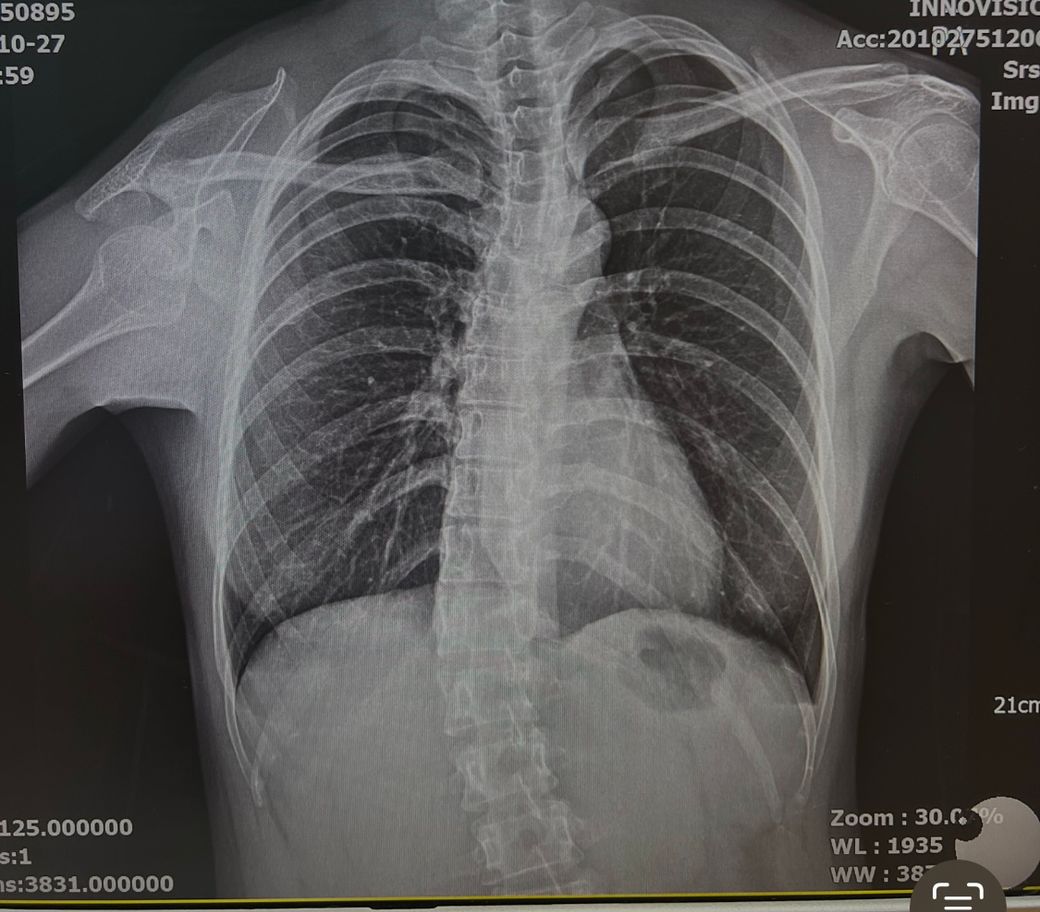

몇 도인지는 모르겠는데 사진처럼 척추측만증이 꽤 심합니다. 임신준비중인데 자연분만 시 무통주사를 놓아도, 제왕절개 시 척추마취를 해도 새우등을 말아서 요추쪽에 맞는데 척추측만은 실패하는 경우가 많아 전신마취 하는 경우도 있다더라구요ㅠㅠ 아직 임신도 안했는데 그런 생각하니 너무 무섭습니다.. 저 정도면 척추마취 불가능한 정도인가요ㅠ

척추측만증이 척추마취의 금기는 아닙니다. 흉추 쪽이 휘어있는 것으로 보이나 요추는 비교적 휜 정도가 크지 않아서 척추마취가 가능합니다. 다만 측만증이 없는 사람에 비해 난이도가 높아질 수 있습니다. 척추 측만보다는 척추협착증인 경우 척추뼈 사이 공간이 좁아 잘 안 들어가는 경우가 많습니다. 작성자님 사진으로 보았을 때 척추마취가 불가능할 정도는 아닌 것으로 보입니다.

척추의 휘어진 각도와 휘어진 부위에 따라 마취가 가능한지 여부가 달라지며, 일반적으로 휘어진 각도가 20~40도 이하라면 척추마취가 성공적으로 시행될 가능성이 높습니다. 척추측만증이 있으면 척추 사이의 공간이 비뚤어져 있어서 바늘을 정확히 삽입하기 어렵기 때문이고, 척추가 휘어져 있다 하더라도 숙련된 마취과 전문의라면 초음파를 사용하여 마취 부위를 찾는 방법을 선택할 수 있습니다.

척추 만곡의 각도가 40도이상인 경우에는 척추마취가 어려운 경우가 존재하지만, 질문자분이 올려주신 사진을 참고했을 때에는 크게 문제가 되지는 않을 것으로 생각됩니다. 우려가 되는 부분이 있으시다면, 수술 전 진료시에 주치의와 이 부분에 관해수 상딤을 해보시는 것을 추천드립니다.